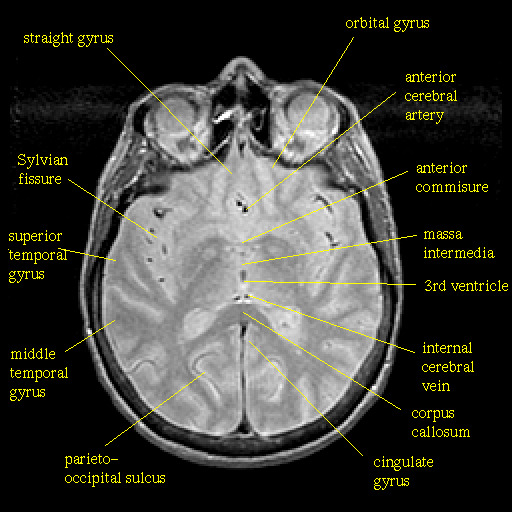

Proton density-weighted structural MR: Slice 27

Slice 27